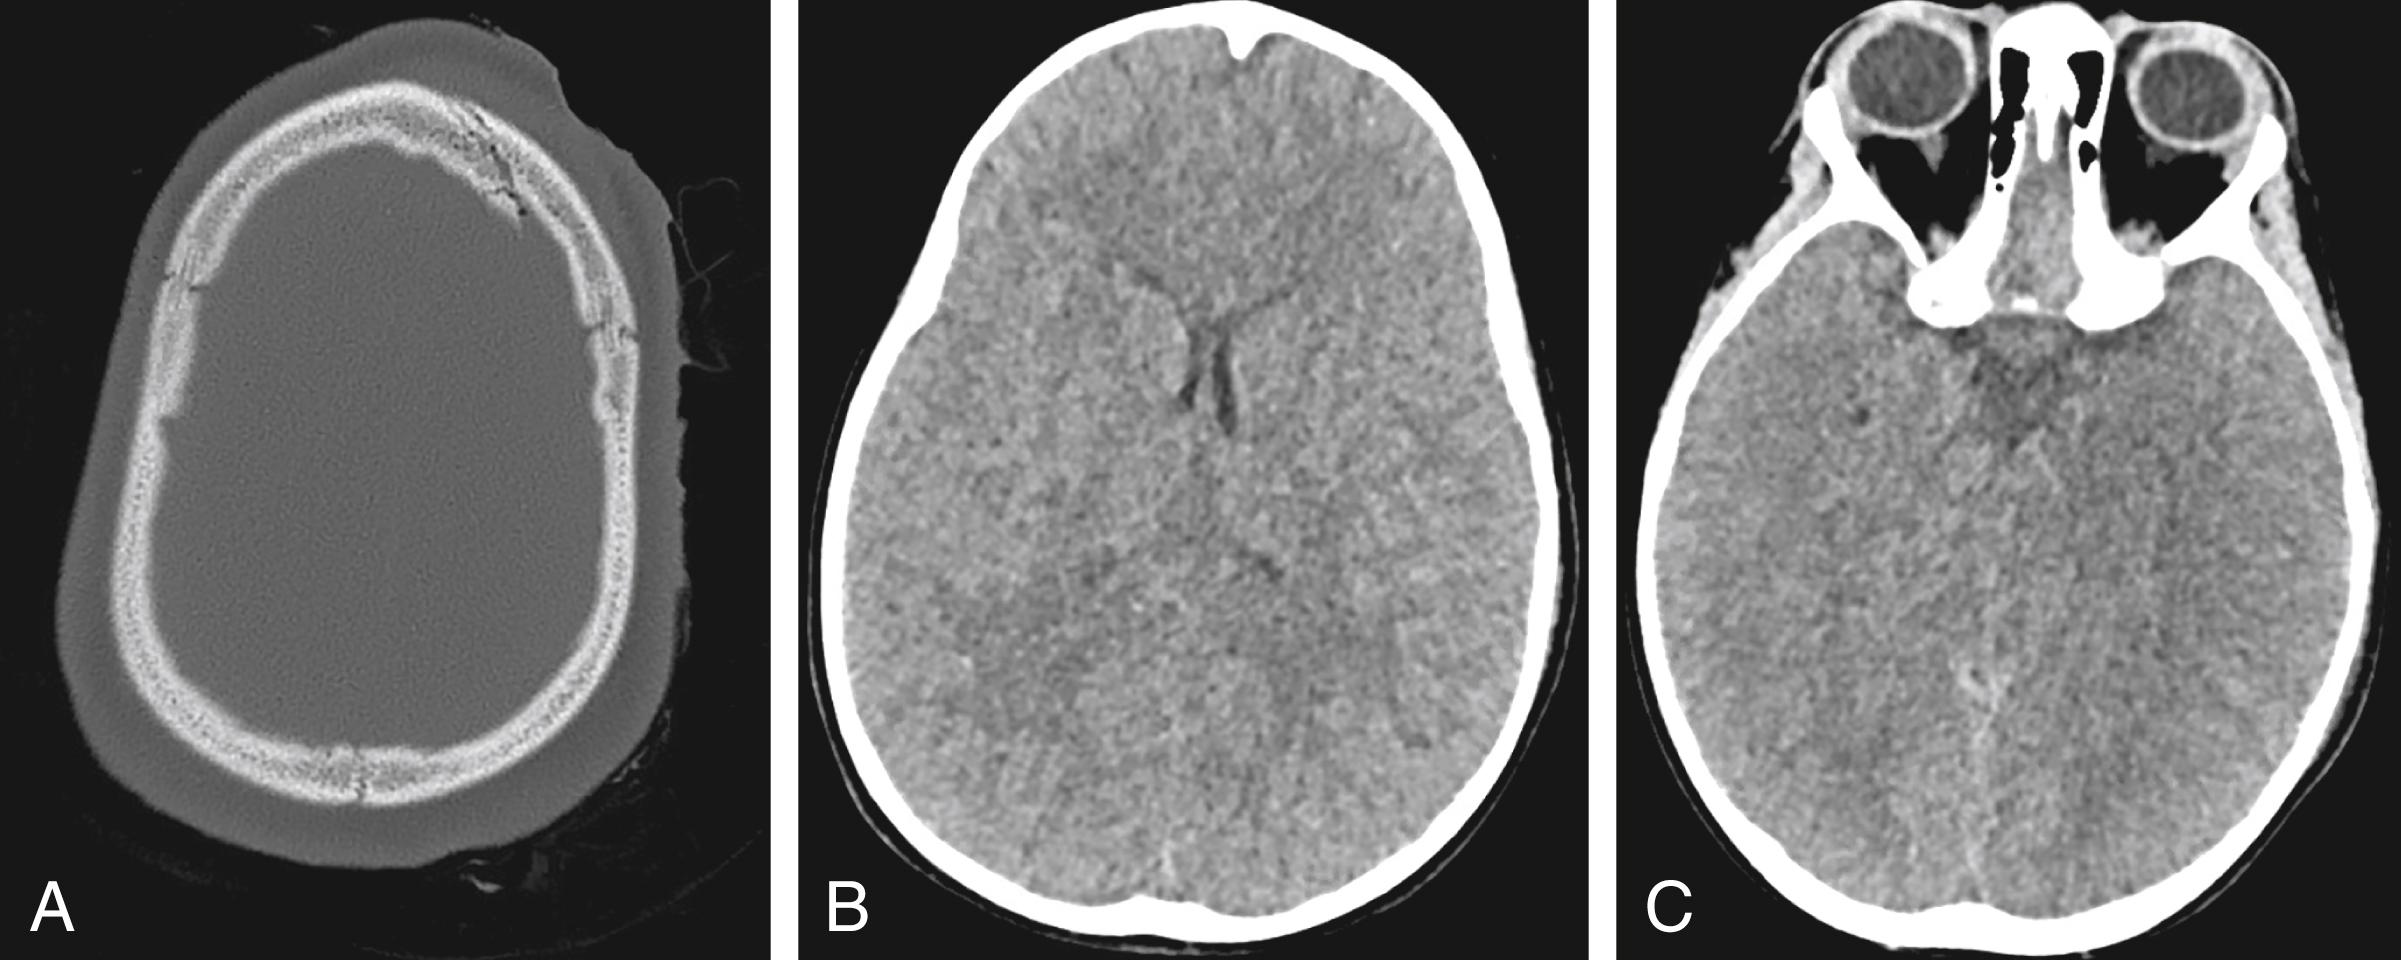

Figure 4.1, Axial head CT without contrast demonstrates a minimally displaced left frontal fracture (A) without evidence of large intracranial hemorrhage (B, C).